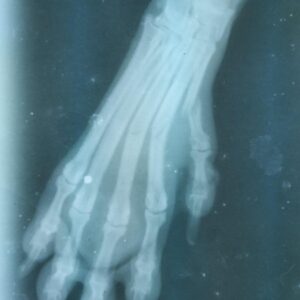

Tak, po wielu godzinach w pułapce, zakrwawioną, z rozerwanymi przez druty bokami, znaleźli ją wolontariusze schroniska. Udało im się oswobodzić Pandę i natychmiast przetransportowali ją do kliniki weterynaryjnej. Na miejscu okazało się, że również jedna z łap wymaga intensywnej terapii – na skutek długotrwałego ucisku została pozbawiona normalnego przepływu krwi. Mimo usilnych starań lekarzy nie udało się przywrócić krążenia w łapie. Zaczęła rozwijać się w niej martwica tkanek. Jedynym wyjściem pozostała amputacja.